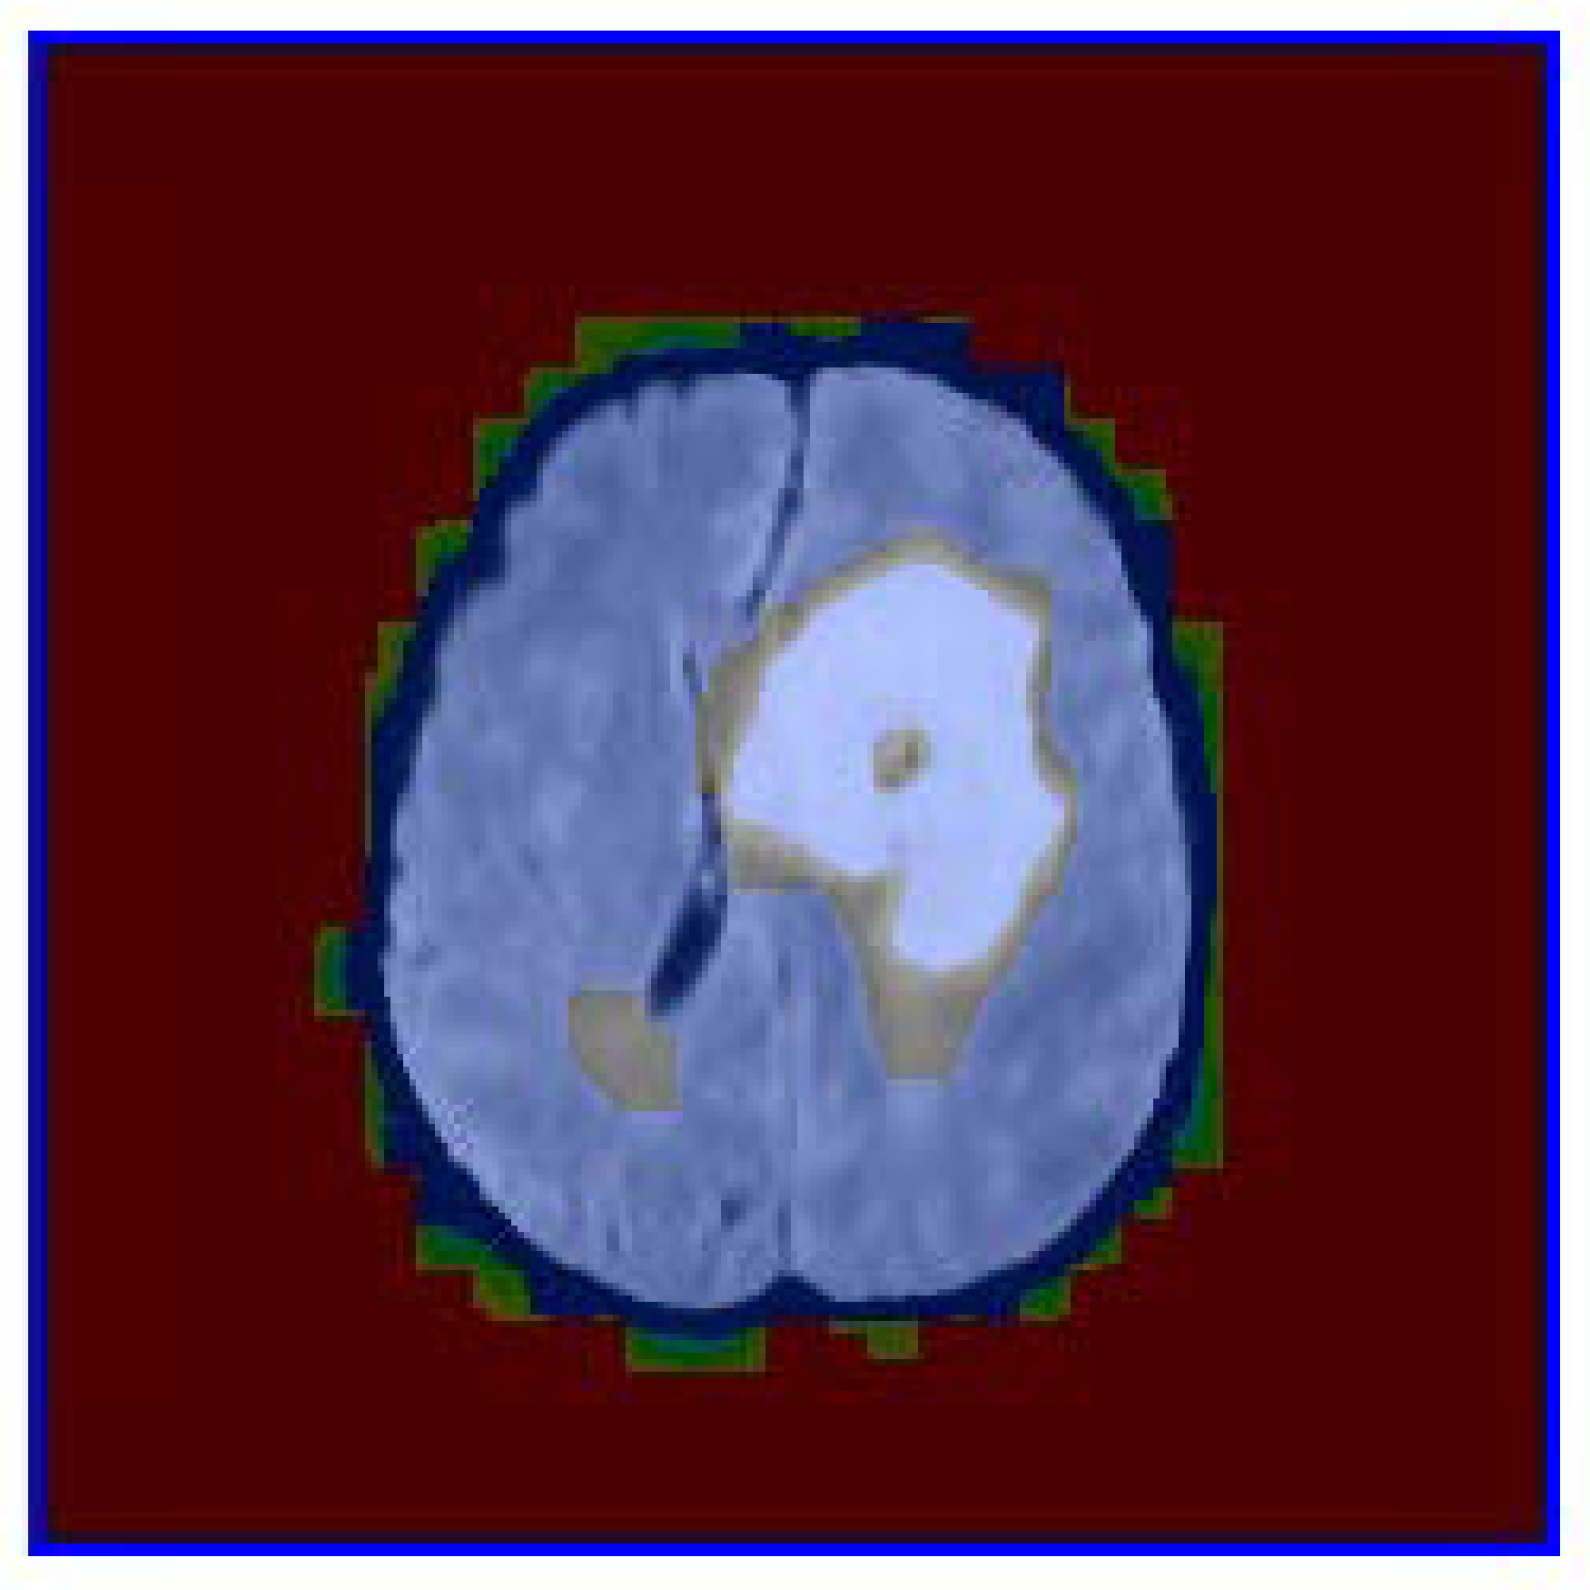

The proposed framework was evaluated on a dataset of brain tumor images. Figure 1 shows the binary mask of the segmented nodule, while Figure 2 presents the color-coded visualization of the segmentation overlaid on the original image. Quantitative metrics, such as area, perimeter, and circularity, were computed for each segmented nodule.

The color-coded visualization in Figure 2 provides additional insights into the segmentation process. The green regions correspond to areas with high probability values derived from the GLCM-based texture analysis. These regions align well with the nodule’s structure, confirming that texture features such as homogeneity and energy are effective in distinguishing nodules from healthy tissue. The blue contours further emphasize the accuracy of the segmentation, as they closely follow the nodule’s edges.

Figure 2. Color-coded visualization of the segmentation overlaid on the original image. The green regions indicate areas with a high probability of being part of the nodule, while the blue contours highlight the boundaries of the segmented region. This visualization aids in the interpretation of the segmentation results, providing a clear distinction between the nodule and the background tissue.

Preprints 153268 g002